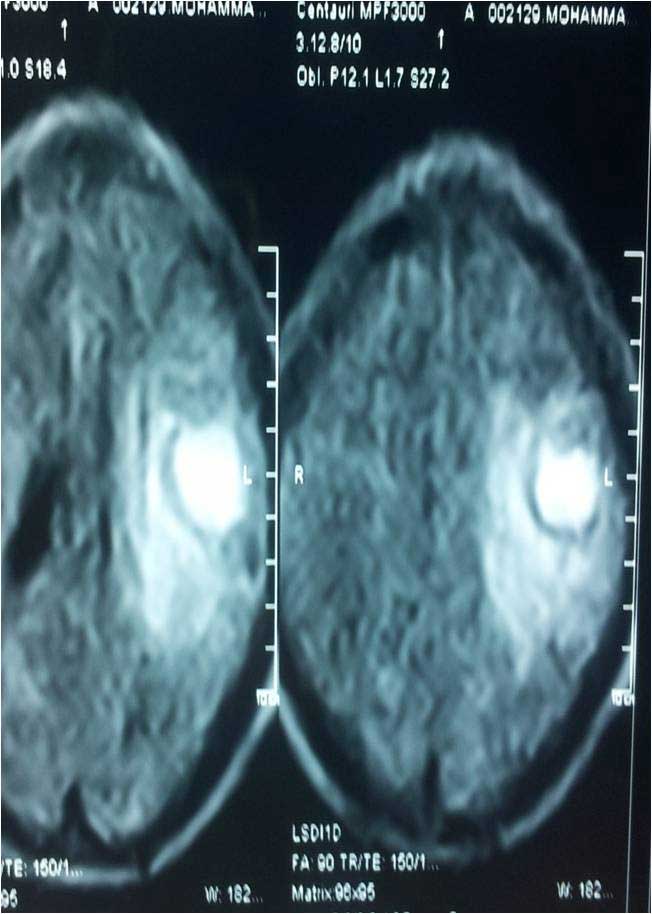

Brain Abscess Brain Abscess Post OP 2 Clinical Intra OP ,After Excising The Granuloma Intaop Scalp Abscess CT Scalp Abscess Cerebellar Abscess Post OP Clinical Cerebellar Abscess Brain TB Granuloma Post OP CT Scan Brain Infection Brain Abscess Preop MRI 2 Brain Abscess PRE OP Clinical 1 Brain Abscess PRE OP Brain Abscess Intraop 2 Brain Abscess Following Shunt Temporal Abscess T2W of TB Granuloma Scalp Abscess Preop CT Marking PRW OP MRI of TB Granuloma Post OP Clinical Photo Post OP Cerebellar Abscess Post OP Brain Abscess Intraop Specimen of Granuloma